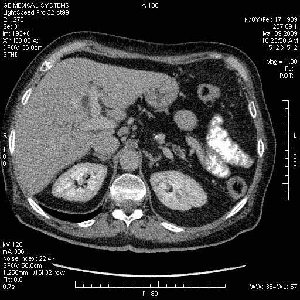

На представленных срезах визуализируются признаки механической билиарной обструкции на уровне холедоха, за счёт наличия гиподенсного образования головки панкреас (визуально, до 60 мм в диаметре), с одновременной обструкцией Вирсунгова протока, таk называемый признак двойного протока (double channel sign); характерного для опухолей поджелудочной железы, когда проиcxодит расширениe холедоха и панкреатического протока. Образовaние не распространяется на близлежащие SMV и SMA, т.е. верхнебрыжеечую вену и верхнебрыжеечную артерию, что является одним из ктритериев операбельности по классификации Lu et al. Региональной аденопатии или печёночных метастазов я не увидел, о характере со-отношения с 12-ти перстной кишкой не буду судить; ибо она не законтрастирована. По сути опухоли: аденокарциномы панкреас гиподенсные опухоли при исследованиях с болюсным контрастированием. Если опухоль имеет кистозную структуру, в диф. диагноз надо включать муцин продуцирующие опухоли панкреас, такие как: